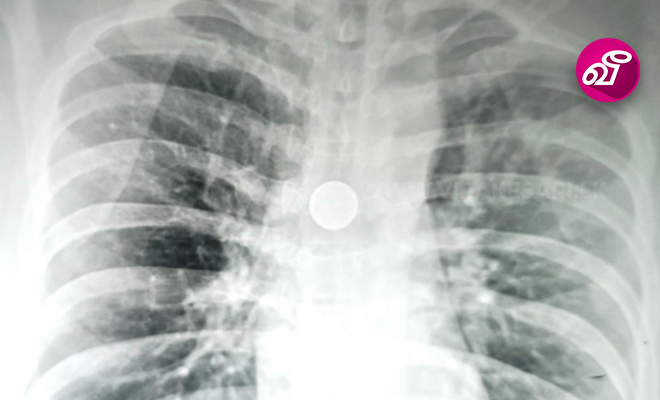

அவரை பரிசோதித்த வைத்தியர்கள், மூச்சுக்குழாயில் 25 சதம் நாணயக்குற்றி ஒன்று சிக்கி இருப்பதை கண்டுபிடித்தனர். இதையடுத்து  கடந்த 2ம் திகதி, கார்டியோ - தொராசிக் அறுவை சிகிச்சை மூலம், மூச்சுக்குழாயில் சிக்கியிருந்த நாணயத்தை வெற்றிகரமாக அகற்றியுள்ளனர்.

பாதிக்கப்பட்ட அந்த நபர் தனது 32வது வயதில் நாணயத்தை வாயில் வைத்து உறங்கியபோது அதை விழுங்கி உள்ளார். அதன் காரணமாக அவருக்கு அவ்வப்போது மூச்சுத்திணறல் ஏற்பட்டுள்ளது. கடந்த வாரம் மூச்சுத்திணறல் அதிகரிக்கவே வைத்தியசாலைக்கு சென்றுள்ளார்.